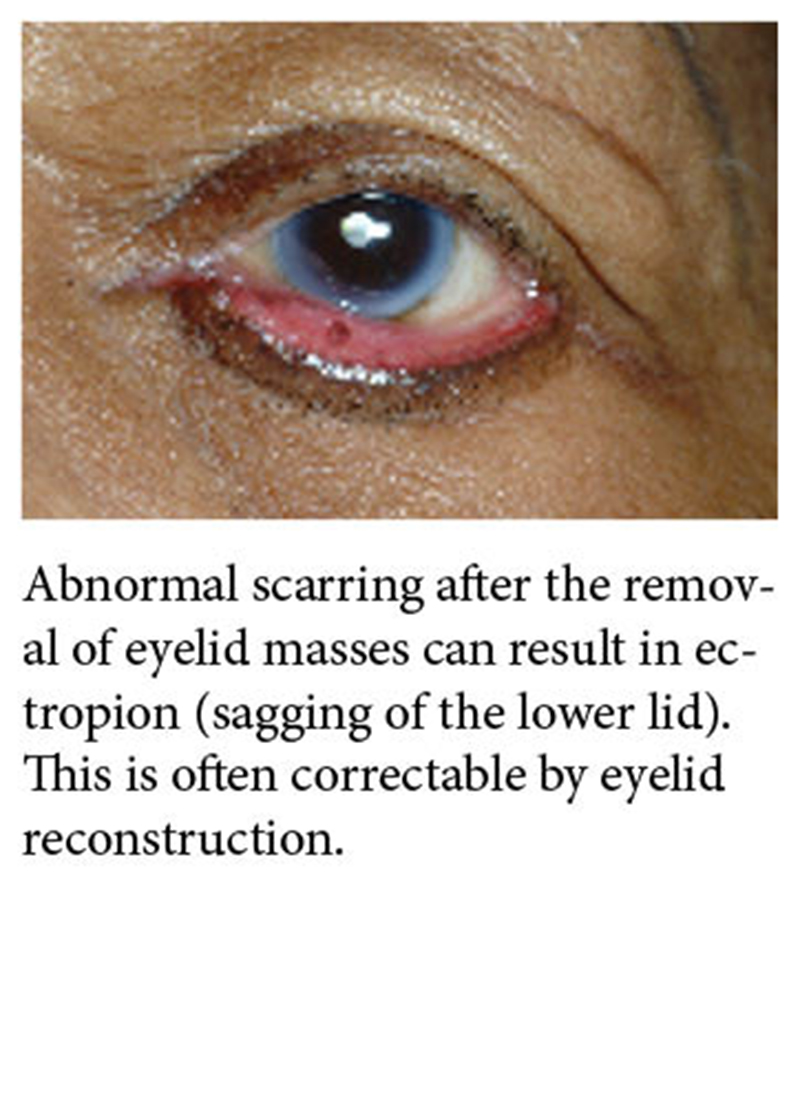

Facial Masses and Scarring

Benign and malignant tumors can arise anywhere on the face or ears.

Mass removal can result in significant facial disfigurement if not reconstructed appropriately immediately after removal.

Issues can arise years later from unexpected consequences of the initial reconstructions.

Unsightly scars can be revised at any time by facial reconstruction.